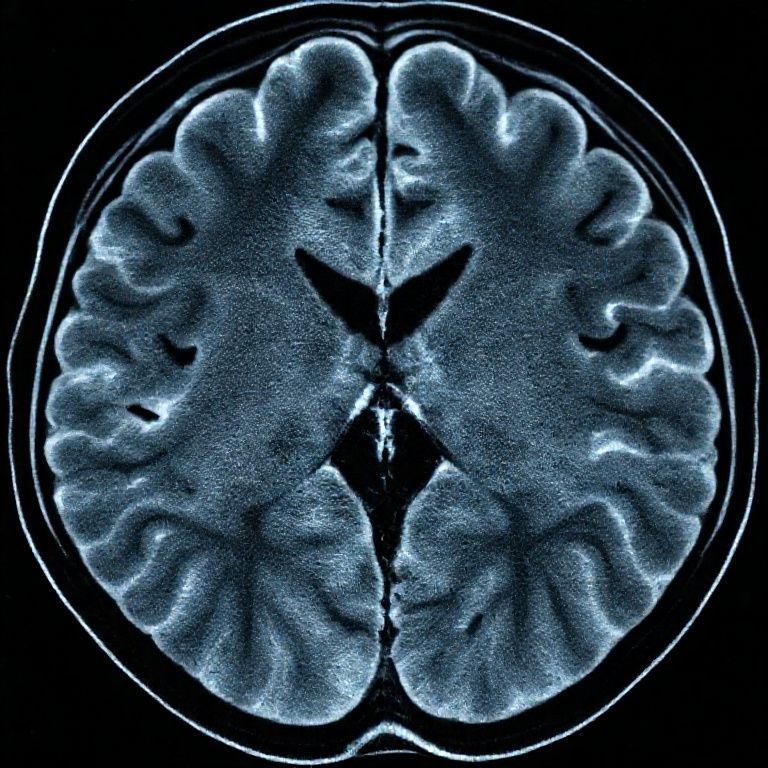

급성 뇌출혈이 의심되는 상황에서는 '시간이 곧 뇌'라는 말이 있을 정도로 신속한 진단이 매우 중요해요. 이때 가장 먼저 고려되고 실제로 가장 많이 사용되는 진단법이 바로 전산화단층촬영, 즉 CT(Computed Tomography) 검사랍니다. CT는 X선을 이용해 신체 내부를 단면으로 촬영하는 방식이에요. 특히 뇌출혈 진단에서는 그 빠른 속도와 출혈 부위를 명확하게 보여주는 능력 때문에 응급 상황에서 그 진가를 발휘해요.

CT 검사는 짧은 시간 안에 뇌 전체를 스캔할 수 있어요. 보통 몇 분 이내에 검사가 완료되기 때문에, 의식이 혼미하거나 불안정한 환자에게도 큰 어려움 없이 적용할 수 있다는 장점이 있죠. 응급실에서는 CT 장비가 비교적 흔하게 구비되어 있고, 검사 비용도 MRI에 비해 저렴한 편이라 접근성이 좋다는 이점도 있어요. 무엇보다 급성 뇌출혈이 발생했을 때, 뇌 속의 피는 CT 영상에서 하얗게 나타나 아주 명확하게 구별돼요. 이러한 특성 덕분에 의료진은 환자가 뇌경색인지 뇌출혈인지 빠르게 감별할 수 있고, 이는 치료 방향을 결정하는 데 결정적인 역할을 해요.

예를 들어, 뇌졸중 증상으로 응급실을 찾은 환자의 경우, CT를 통해 뇌출혈이 없음을 확인해야만 혈전을 녹이는 혈전용해제 치료(뇌경색의 주요 치료법)를 안전하게 시작할 수 있어요. 만약 뇌출혈이 있는 상태에서 혈전용해제를 투여하면 출혈을 더욱 악화시킬 수 있기 때문이에요. 이처럼 CT는 급성 뇌졸중 환자들 중에서 뇌출혈을 '제외'하는 선별 진단법으로 아주 중요한 역할을 한답니다. 또한, 뇌출혈뿐만 아니라 외상으로 인한 두개골 골절이나 다른 급성 손상을 확인하는 데에도 CT가 MRI보다 훨씬 우수하다고 알려져 있어요. 뼈 구조를 선명하게 보여주는 CT의 특성 덕분이죠.

하지만 CT 검사에도 한계점은 존재해요. X선을 이용하기 때문에 방사선에 노출된다는 점이 가장 큰 단점이에요. 물론 한 번의 검사로 인체에 미치는 영향은 미미하지만, 반복적인 검사나 소아 환자에게는 주의가 필요할 수 있어요. 또한, CT는 뇌의 연조직(soft tissue)을 MRI만큼 상세하게 보여주지는 못해요. 예를 들어, 뇌출혈이 발생한 후 시간이 지나 혈액이 분해되면서 생기는 미묘한 변화나, 아주 작은 병변, 뇌간이나 후두와 같은 특정 부위의 병변은 CT만으로는 놓칠 수 있는 경우가 있답니다. 그리고 조영제를 사용할 경우 알레르기 반응의 위험도 있고요. 하지만 급성기 뇌출혈 진단이라는 특수한 목적에 있어서는 이러한 한계점에도 불구하고 CT의 역할은 대체 불가능하다고 볼 수 있어요.

실제로 많은 의료기관에서 응급 환자가 뇌졸중 증상을 보이면, 가장 먼저 CT 촬영을 진행해요. 이는 신속한 진단을 통해 생명을 살리는 데 필수적인 과정이에요. CT는 뇌출혈의 유무, 위치, 크기 등을 빠르게 파악하여, 의료진이 필요한 조치를 즉시 취할 수 있도록 도와준답니다. 특히 대형 병원의 응급실에는 24시간 CT 검사가 가능하도록 운영하고 있는 곳이 많아요. 만약 CT 검사 결과 뇌출혈이 확인된다면, 추가적인 치료 계획을 세우게 되는데, 이때 환자의 상태나 출혈의 정도에 따라 수술적 치료가 필요할 수도 있어요. 이 모든 결정은 CT 검사 결과에 기반하여 신속하게 이루어지는 거죠.